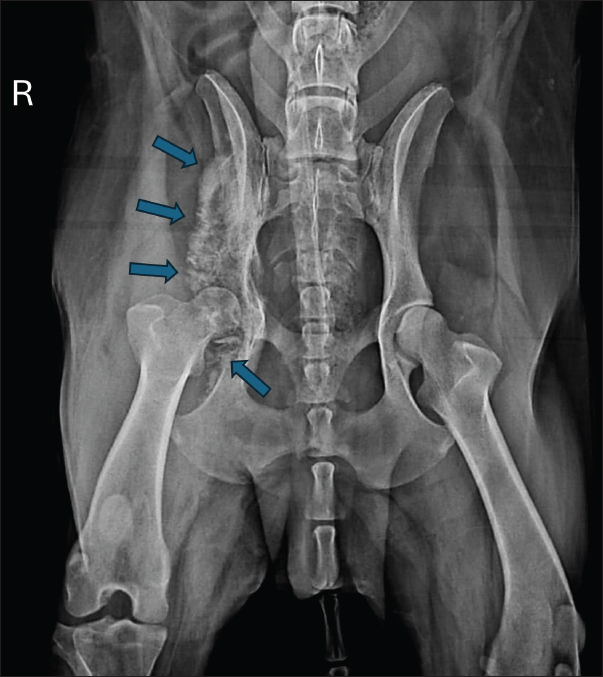

Based on clinical and radiographic improvement, itraconazole and gabapentin were continued for an additional 30 days, while cephalexin was discontinued to minimize potential adverse effects. After 60 days of treatment, follow-up radiographs demonstrated continued gradual reduction in osteolysis (Fig. 5). Therapy was extended for an additional 3 months, with ongoing clinical improvement.

Fig. 5. Radiographic examination of the dog 60 days after initiation of itraconazole treatment, showing ongoing, albeit slight, reduction of osteolytic areas.